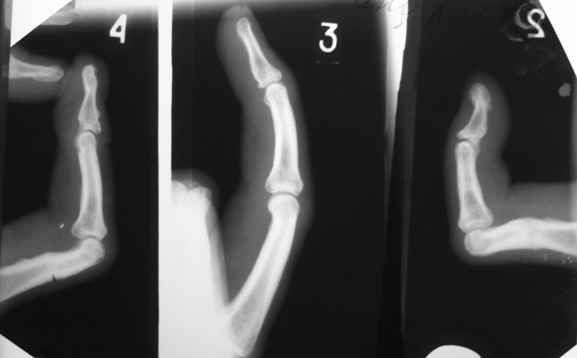

Уважаемые коллеги!Обратился больной с контрактурой 2-4 пальцев кисти. Травма год назад - рука попала в шнек. Планируется оперативное лечение.

При размещении с рисунков "исчезли" подписи, поэтому дополнительно указываю, что первая рентгенограмма - снимок после травмы, вторая - состояие на сегодня. На мой взгляд контрактура прежде всего артрогенная, т.к. ПМФС 2-го и 4-го пальцев находятся в подвывихе. Движения, в существующем на сегодня объеме, свободные - даст-ли тендолиз ожидаемый эффект? Стоит-ли начать с аппарата внешней фиксации? Не приведет-ли одномоментный артролиз и последующая попытка вправления при длительно существовавшем подвывихе к раздавливанию суставными поверхностямя друг друга?

Для того, чтобы понять, действительно ли ПМФС находятся в подвывихе, надо сначала сделать четкую боковую рентгенографю сустава. Особенно это касается второго пальца. Да и на мониторе очень плохо видно состояние головки проксимальной фаланги 4 пальца. И что означает такой интересный объем движений в суставах? Объясните - существует ограничение только активных движений ( и каких?) или еще и пассивных?

Ограничение движений одинаковое и активных и пассивных. Движения в указанном объеме свободные. Чем вызвано ограничение понять пока не можем. В боковой проекции досняли - получается, что подвывиха нет. Вопросов, в отношении того, что мешает стало еще больше.

Насколько я понял - у больного имеется сгибательная контрактура 2-4 пальцев, то есть активное и пассивое сгибание этих пальцев практически полное. Но наблюдается ограничение пассивного и, тем более, активного разгибания пальцев, особенно 2 и 4 , в проксимальных межфаланговых суставах. Я так понял? Вы не указали, переломы были открытыми или закрытыми. Были ли повреждения сухожилий сгибателей или разгибателей? Если переломы были закрытые и если больного ну абсолютно не устраивает такое положение пальцев, то можно предложить следующие варианты. 1. Курс физиолечения плюс статические и динамические ( то есть с резиновой тягой) шины. Если больной это все получал и не отмечено положительного эффекта, то можно использовать второй вариант в различных модификациях. 1а- под проводниковой анестезией провести попытку редрессации, но не грубой, чтобы не поломать пальцы. Если редрессация не удается, то выполнить ладонную капсулотомию проксимального межфалангового сустава через 1-2 боковых поперечных разреза по нейтральным линиям пальца. Иногда приходится частично рассекать боковые связки. Опять попытка редрессации. Если снова ничего не получается, то следует обратить внимание на напряженный поверхностный сгибатель пальца. Этот сгибатель через эти же боковые разрезы нужно рассечь. Опять редрессация. Думаю, что в последнем случае Вам повезет. Уффф!

Да, забыл. Третий палец я бы вообще не трогал или ограничился только лишь небольшой редрессацией ( насколько я понял по картинкам и описанию - ограничение пассивно-активной функции на 3 пальце - абсолютно минимальные).

Повреждение было открытым - кисть в перчатке попал в шнек сгоуборочной машины (что-то вроде большой мясорубки). Лечился по месту жительства остеосинтез спицами, ушивание ран. Через три недели спицы удалили. Со слов, сухожилия не шили - документов нет. В рубцах, конечно, и сгибатели и разгибатели. Вот только, как я уже говорил непонятно почему, в доступном объеме, движения совершенно свободные? Например, если разгибатель фиксирован на уровне основной фаланги то почему есть разгибание до середины, а если не фиксирован то что мешает дальше "скользить" и разгибать до конца.